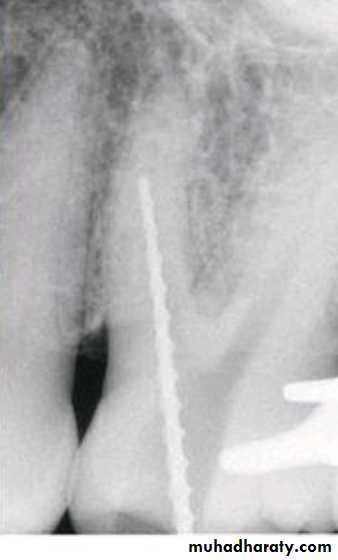

The step-down technique is advocated for cleaning and shaping procedures as it removes coronal interferences and provides coronal taper.

With the pulp chamber filled with irrigant or lubricant, the canal is explored with a small instrument to assess patency and morphology (curvature). The working length can be established at this time.

The coronal one third of the canal is then flared with Gates-Glidden drills or rotary files of greater taper (.06, .08, or .10).

Step-Down Technique

A large file (such as No. 70) is then placed in the canal, and a watch-winding motion is used until resistance is encountered.

The process is repeated with sequentially smaller files until the apical portion of the canal is reached. The working length is checked again.

The apical portion of the canal can now be prepared by enlarging the canal at the corrected working length.